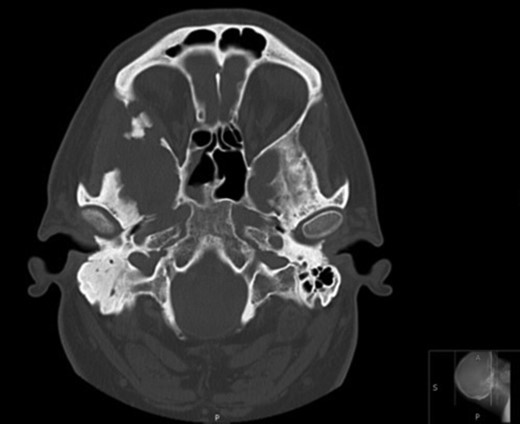

Axial CT images demonstrating bony involvement of the right mastoid and greater wing of the sphenoid.

Due to the extensive nature of the findings, a magnetic resonance imaging (MRI) scan of the head was undertaken and demonstrated bony erosion of the lateral wall of the right orbit, right superior rectus muscle abutment and minimal involvement of the antero-inferior surface of the temporal lobe. The appearances were suggestive of fibrous dysplasia, chronic inflammatory/infective pathology or less likely metastatic carcinoma.